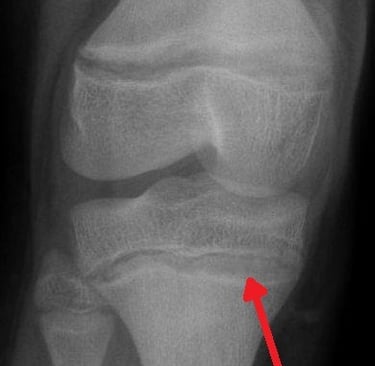

Periferik Yayma (Basofilik Noktalanma):

Mikroskopta eritrositlerin içinde "karabiber serpilmiş gibi" mavi noktalar görülür.

LR+ (Pozitif Olasılık Oranı): 15-20. (Yani bu bulgu varsa, kurşun zehirlenmesi olasılığı 20 kat artar. Çok güçlü bir kanıttır).